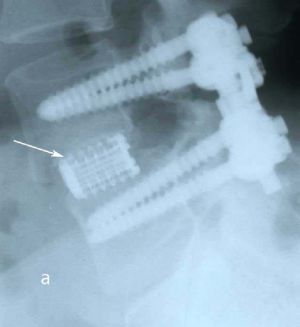

Пациенту выполнено оперативное лечение: удаление секвестрированной парамедианной грыжи мп диска L5-S1 слева из минидоступа, миниинвазивная транспедикулярная фиксация L5-S1 титановой конструкцией.

При контрольной рентгенограмме отмечено правильное положение транспедикулярной системы и кейджа на уровне L5-S1 позвонков. (Рис.9)

Рис. 10 a. Ренгенограмма поясничного отдела позвоночника в боковой (a) и прямой (b) проекции. Транспедикулярная фиксация L5-S1 позвонков титановой конструкцией канюлированными винтами, межтеловая фиксация позвонков кейджем из PEEK-керамики. Стрелкой указано положение ренген–негативного кейджа, видны титановые метки кейджа. Рис. 10 b. Ренгенограмма поясничного отдела позвоночника в боковой (a) и прямой (b) проекции. Транспедикулярная фиксация L5-S1 позвонков титановой конструкцией канюлированными винтами, межтеловая фиксация позвонков кейджем из PEEK-керамики. Стрелкой указано положение ренген–негативного кейджа, видны титановые метки кейджа.

Рис. 9 a,b. Ренгенограмма поясничного отдела позвоночника в боковой (a) и прямой (b) проекции. Транспедикулярная фиксация L5-S1 позвонков титановой конструкцией канюлированными винтами, межтеловая фиксация позвонков кейджем из PEEK-керамики. Стрелкой указано положение ренген–негативного кейджа, видны титановые метки кейджа.